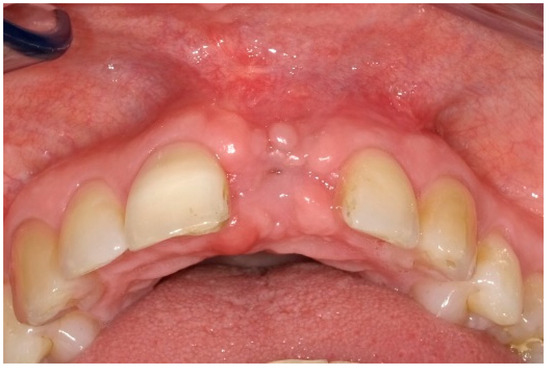

| Mean peri-implant pocket depth at Tpre (mm) | 8.5 | 8.5 | 8.5 |

| Mean peri-implant pocket depth at T9 (mm) | 3.2 | 3.5 | 3.0 |

| Mean peri-implant pocket depth at T12 (mm) | 3.2 | 4.0 | 3.0 |

| Deepest peri-implant pocket at Tpre (mm) | 11.0 | 10.0 | 9.0 |

| Deepest peri-implant pocket at T9 (mm) | 4.0 | 6.0 | 4.0 |

| Deepest peri-implant pocket at T12 (mm) | 5.0 | 6.0 | 4.0 |

| Peri-implant BS at Tpre (%) | 100.0 | 100.0 | 100.0 |

| Peri-implant BS at T9 (%) | 100.0 | 33.3 | 16.7 |

| Peri-implant BS at T12 (%) | 16.7 | 83.3 | 33.3 |

| Peri-implant SS at Tpre (%) | 16.7 | 66.7 | 50.0 |

| Peri-implant SS at T9 (%) | 0.0 | 0.0 | 0.0 |

| Peri-implant SS at T12 (%) | 0.0 | 0.0 | 0.0 |

| Midfacial mucosa level at Tpre (mm) | 3.0 | 2.0 | 5.0 |

| Midfacial mucosa level at T9 (mm) | 5.0 | 6.0 | 6.0 |

| Midfacial mucosa level at T12 (mm) | 5.0 | 6.0 | 6.0 |